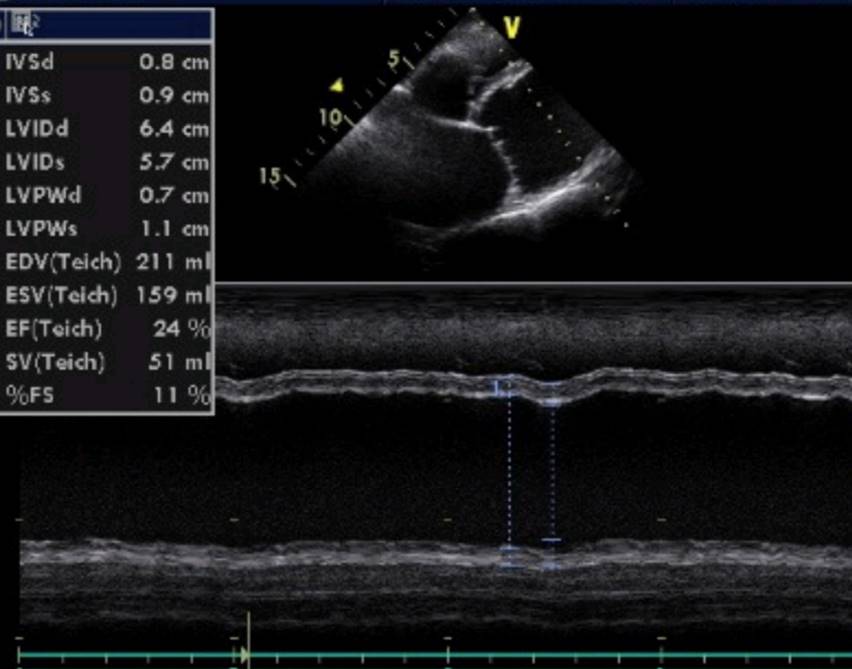

Окончательный диагноз ставится на основании ультразвукового исследования сердца (ЭХО КГ).